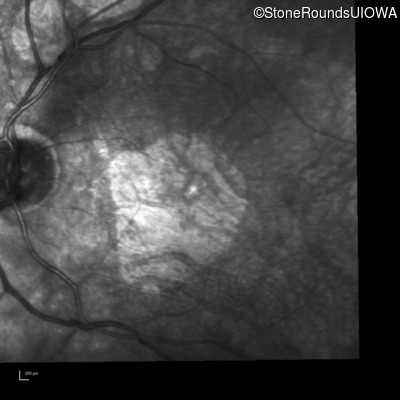

Infrared Fundus Photograph - Right - 20/80

Exemplar